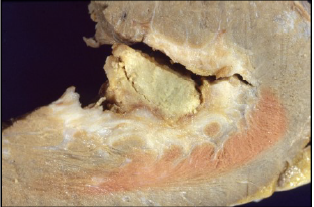

Placche aterosclerotiche, una ulcerata

(freccia) e strie lipidiche;

Placche

ateroma siche

ulcerate e

complicate;

placca ateroma sica con ulcera

profonda;

placca fibroateromasica, con un cappuccio

fibroso sottile (spessore < 65 μm), ti tipo

eccentrico, con ateroma relativamente

abbondante;